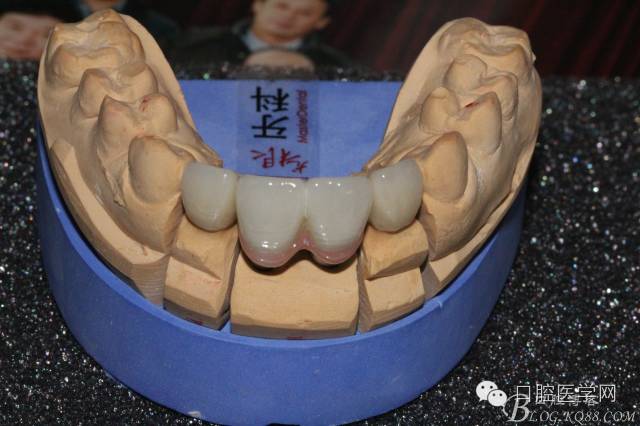

設(shè)計(jì)方案:11.21種植(選用登騰系統(tǒng),GBR植骨)12.22 RCT后樁冠修復(fù),牙齦瓷修復(fù)。

因該患者笑線比較高,不微笑也露出牙齦,所以考慮到美觀,兩顆中切齒上方給做的牙齦瓷。